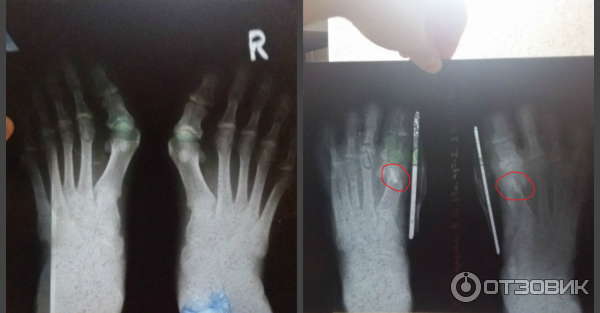

Спицы в пальцы операция

Спицы в пальцы операция 109 фото